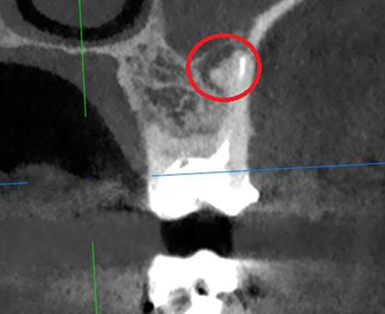

Сохранение зуба при наличии кисты, проростающей в гайморову пазуху

Проблема: У пациента боли в проекции гайморовой пазухи, заложенность носа, боли при пережевывании пищи.

Лечение: Проведено эндодонтическое перелечивание зуба под микроскопом: удалены ранее внесённые материалы, выполнена тщательная механическая и медикаментозная обработка корневых каналов с учётом их анатомии. Особое внимание уделено устранению инфекционного очага (кисты), связанного с воспалением в области гайморовой пазухи. После этого каналы герметично запломбированы, а коронковая часть зуба временно восстановлена для дальнейшего покрытия зуба коронкой.

Результат: После проведённого эндодонтического лечения болевые ощущения при жевании устранены, дискомфорт и давление в области гайморовой пазухи исчезли, восстановилось нормальное носовое дыхание. Зуб сохранён, его функция восстановлена. После фиксации коронки полностью восстановлены анатомическая форма и жевательная эффективность, нагрузка распределяется корректно.